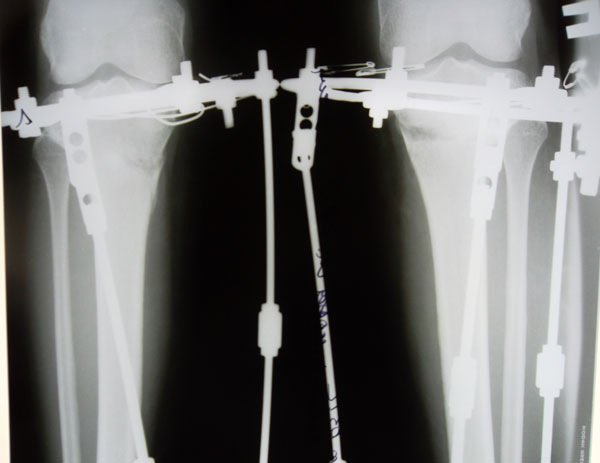

Рентгеновские снимки в прямой проекции.